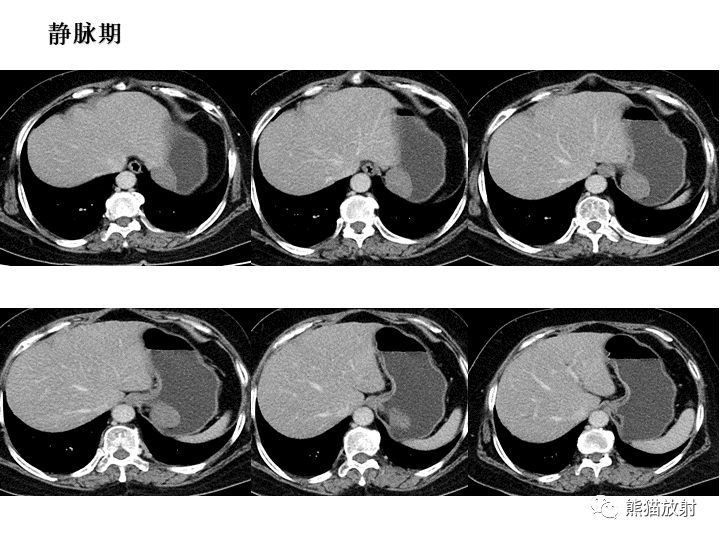

【病例】胃间质瘤VS神经鞘瘤-3